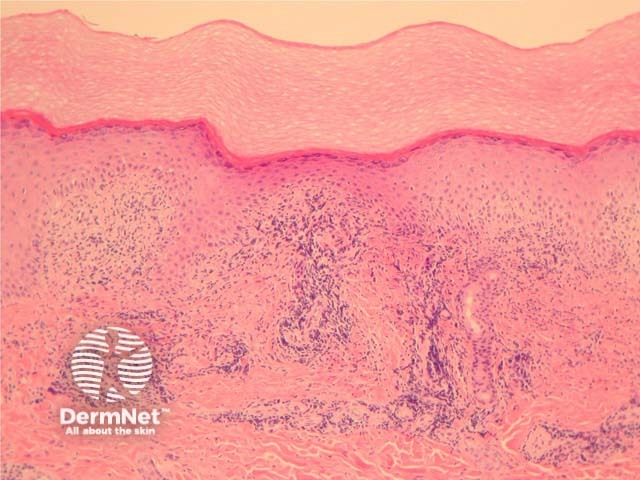

In perniosis, sections show acral skin with a dense superficial and deep lymphocytic infiltrate (figure 1). Subepidermal oedema may be marked. The characteristic feature is lymphocytic perivascular infiltrate within the dermis and sometimes extending to the subcutis (figures 2, 3). This is thought by some authors to represent the one true “lymphocytic vasculitis”, as there may be well established fibrinoid change and thrombosis can occur. There may be numerous eosinophils in early lesions (figure 4).

Figure 1